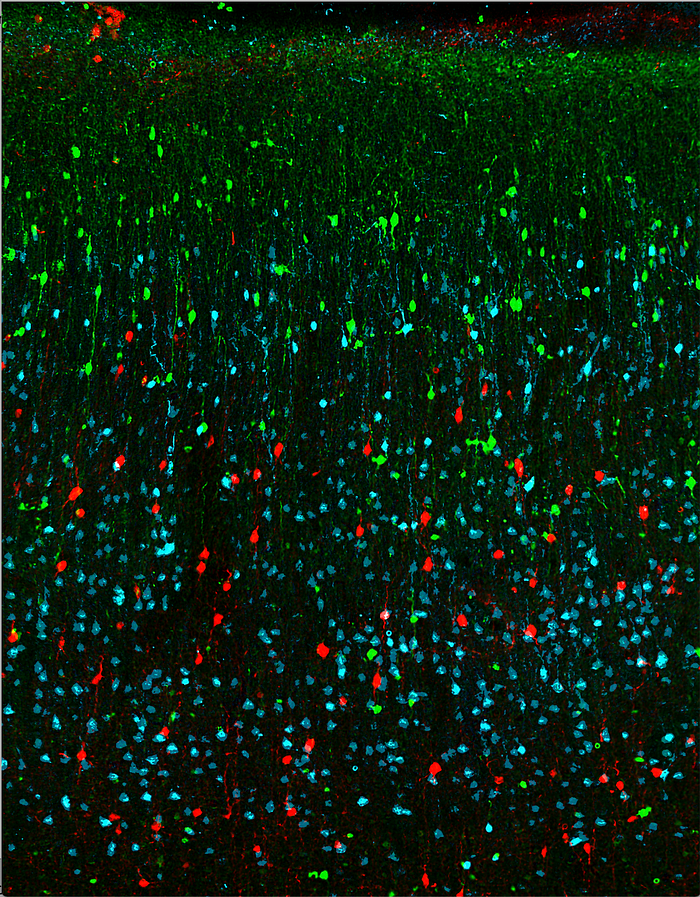

The researchers identified area 32 using neural tracers to visualize the connections between cognitive (DLPFC) and emotional (area 25) brain regions in rhesus monkeys. Their discovery helps us better understand what makes certain people more susceptible to depression — and can inform different treatment approaches.

In healthy brains, the DLPFC signals area 32 to balance area 25 activity, enabling emotional stability. Emotional balance goes haywire in mood disorders like depression, leading to unchecked negative emotions and an inability to break out of rumination. This runaway negative emotion is often caused by an overactive area 25. The researchers speculate that in individuals where area 32 has weaker connections with DLPFC and area 25, emotional regulation may be more difficult — perhaps rendering individuals vulnerable to depression. Furthermore, identifying and evaluating the strength of area 32’s connections with DLPFC and area 25 can help inform which treatment approach to take for people suffering from depression — ranging from cognitive behavior therapy, to medication, to deep brain stimulation.

So, what do these critical interactions between brain regions actually look like? The researchers take us into their lab for an inside-look: